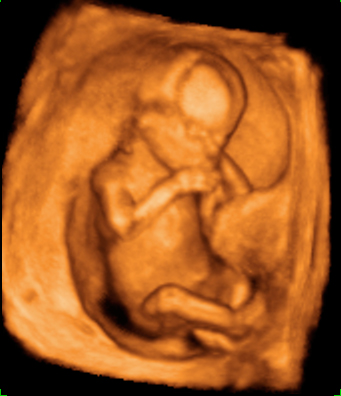

Ecografía 4D semana 12: Bebé moviendo brazos y piernas

Destaca la gran vitalidad del feto

La ecografía 4D muestra un bebé de 12 semanas de gestación moviéndose con gran vitalidad dentro del útero materno. Se percibe perfectamente que el feto tiene formadas todas sus estructuras básicas, a falta de que maduren a lo largo del embarazo.

Ecografía en 4D de bebé de 12 semanas moviendo brazos y piernas

La vitalidad del bebé es increíble. Mueve brazos y piernas con energía, como si estuviera nadando, o haciendo un "sprint" final. En realidad está apoyado en la pared uterina de su madre. Se perciben las estructuras básicas del feto con gran claridad: cabeza, aún muy grande respecto al cuerpo, tronco y extremidades. Este movimiento es uno de los signos de vitalidad fetal que los ecografistas siempre evalúan en sus exploraciones.